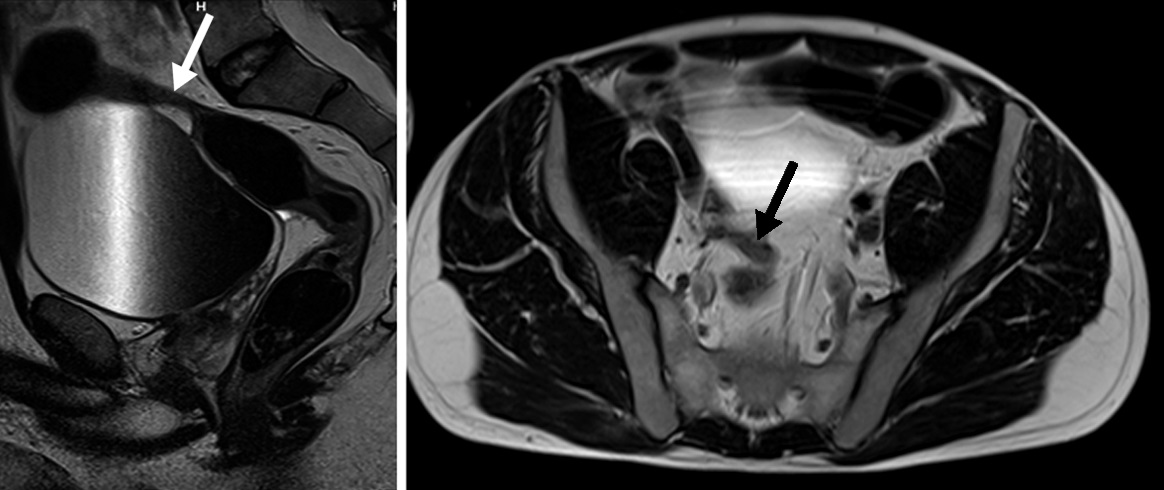

Figura 1

a y b) Secuencia coronal y axial en eco de gradiente

coherente. Intestino delgado normal distendido con

señal intraluminal homogénea. Se observa el artefacto

en tinta china periférico que no debe confundirse con

engrosamientos parietales (flecha blanca).

c) Secuencia T2 coronal sin saturación grasa

d) Axial con saturación grasa. Intestino delgado

normal con vacíos de señal intraluminal por efecto del

peristaltismo normales en estas secuencias.

e) Secuencia T1 coronal con gadolinio y saturación grasa. Se idenjpgica el realce parietal habitual.